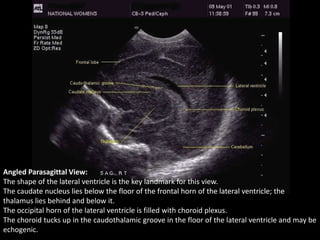

Angled Parasagittal View:

The shape of the lateral ventricle is the key landmark for this view.

The caudate nucleus lies below the floor of the frontal horn of the lateral ventricle; the

thalamus lies behind and below it.

The occipital horn of the lateral ventricle is filled with choroid plexus.

The choroid tucks up in the caudothalamic groove in the floor of the lateral ventricle and may be

echogenic.

Angled Parasagittal View: Theshape of the lateral ventricle is the key landmark for this view. The caudate nucleus lies below the floor of the frontal horn of the lateral ventricle; the thalamus lies behind and below it. The occipital horn of the lateral ventricle is filled with choroid plexus. The choroid tucks up in the caudothalamic groove in the floor of the lateral ventricle and may be echogenic.